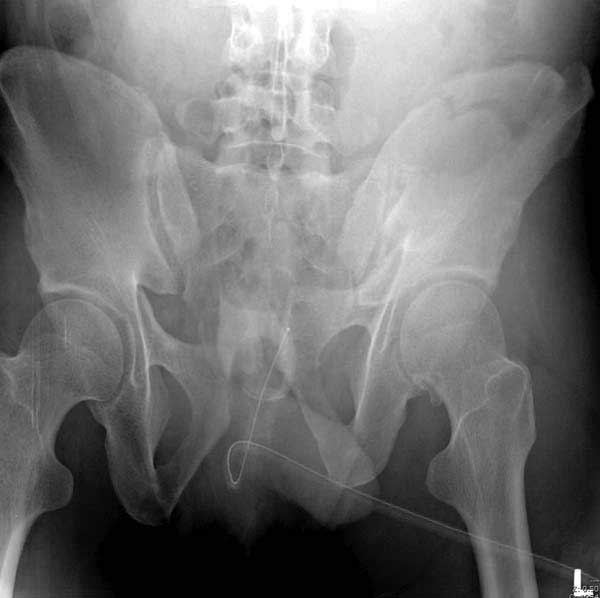

Рецидив смещения - признак несостоятельности фиксации. В первую очередь из-за ранней нагрузки, или когда имеется нестабильность в тазовом кольце. При повреждениях транссакральных структур сзади, фиксация переднего полукольца-симфиза облегчает репозицию, но не гарантирует стабильность. Нестабильное тазовое кольцо ранее или поздно срывает фиксацию симфиза.

Подробное изучение инлет и оутлет, а также КТ срезов, поможет разобраться в диагностике. Без обследования случай усложнится. Операция непростая, кроме технических навыков, надо иметь стандартные инструменты для операции.

Уважаемый проф. Djoldas Kuldjanov,подскажите насколько стабильна фиксация в аппарате при таком характере перелома? Ведь линия перелома проходит через крыло и тело подвздошной кости и учитывая повреждение переднего полукольца формируется "свободный костный сектор". Как то я зафиксировал подобный перелом так же аппаратом на 2-х стержнях, однако получил замечание коллег на нестабильность фиксации. Предложили вариант с введением стержней в задние структуры с замыканием на переднюю раму (модификация аппарата это позволяет). Хотелось бы услышать Ваше мнение.